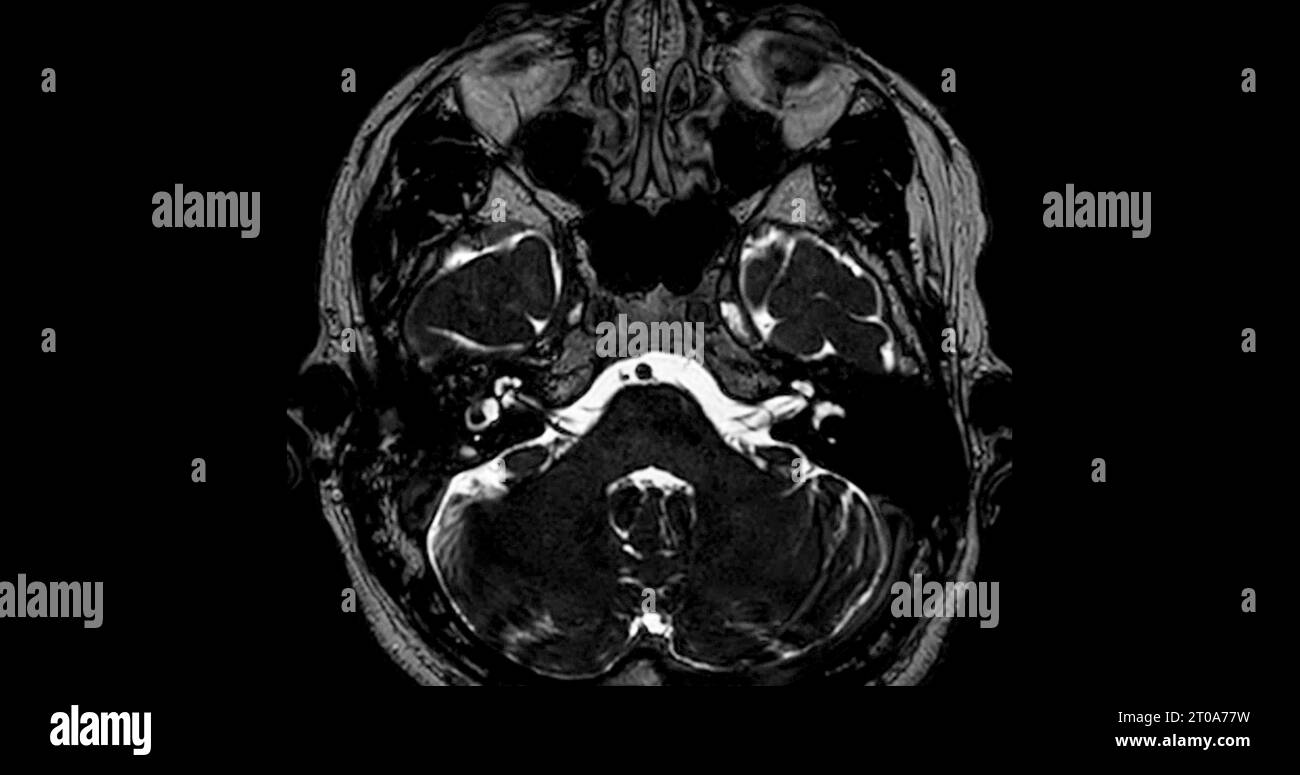

MRI scan of the internal auditory canal (IAC Stock Photo Alamy What Is Internal Auditory Canal The internal acoustic canal (iac), also known as the internal auditory canal or meatus (iam), is a bony canal within the. The posterior portion of the internal auditory canal. Which is a nerve that goes to the semicircular canals. The iac includes arteries and nerves. The purpose of this review is to provide an overview of the most useful mri. What Is Internal Auditory Canal.

MRI scan of the internal auditory canal (IAC Stock Photo Alamy What Is Internal Auditory Canal Review of internal auditory canal (iac) anatomy. Which is a nerve that goes to the semicircular canals. The most easily seen structures are the. The posterior portion of the internal auditory canal. The iac includes arteries and nerves. The internal acoustic canal (iac), also known as the internal auditory canal or meatus (iam), is a bony canal within the. The. What Is Internal Auditory Canal.

MRI scan of the internal auditory canal (IAC Stock Photo Alamy What Is Internal Auditory Canal The most easily seen structures are the. Which is a nerve that goes to the semicircular canals. The iac includes arteries and nerves. The posterior portion of the internal auditory canal. Review of internal auditory canal (iac) anatomy. The purpose of this review is to provide an overview of the most useful mri sequences for internal auditory canal and labyrinthine. What Is Internal Auditory Canal.